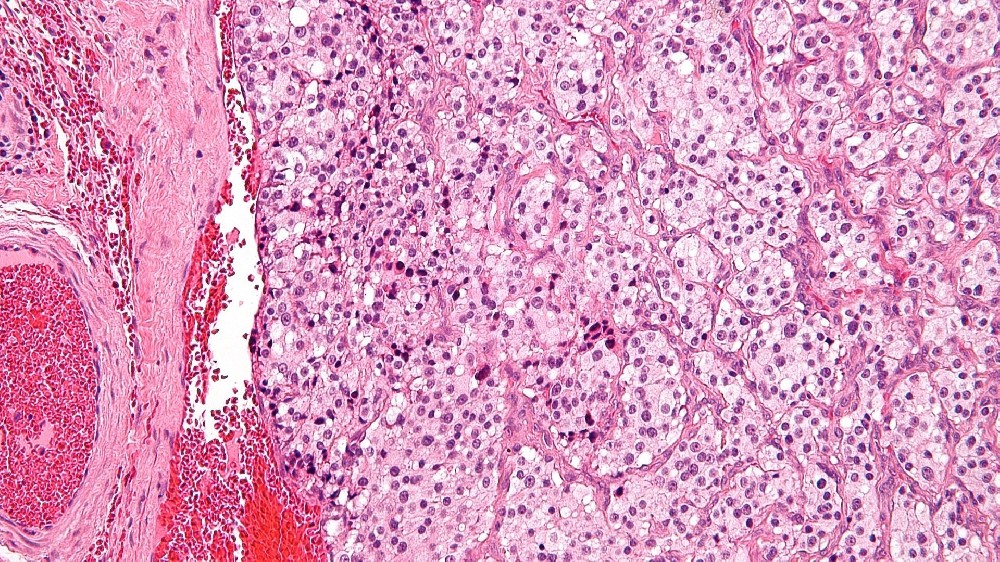

副膽管瘤是一種不常見的神經內分泌腫瘤,由副膽管內的絨毛素細胞所引起。這些專門的細胞通常透過分泌腎上腺素和去甲腎上腺素等兒茶酚胺來調節身體的基本功能,如血壓、心率和壓力反應。

代謝脆弱性和葡萄糖依賴症

在副膽管瘤中觀察到的一個決定性生物特徵是它們對葡萄糖新陳代謝改變的依賴。在缺氧或非缺氧的環境中利用糖酵解使癌細胞具有顯著的生長優勢,在診斷 PET 掃描 (18F-FDG 成像) 中可見大量的葡萄糖攝取就是明證。利用癌細胞對葡萄糖的依賴性的針對性療法,也就是所謂的代謝腫瘤學,在諾貝爾獎得主(Allison、Semenza)的研究支持下,對治療創新非常重要。